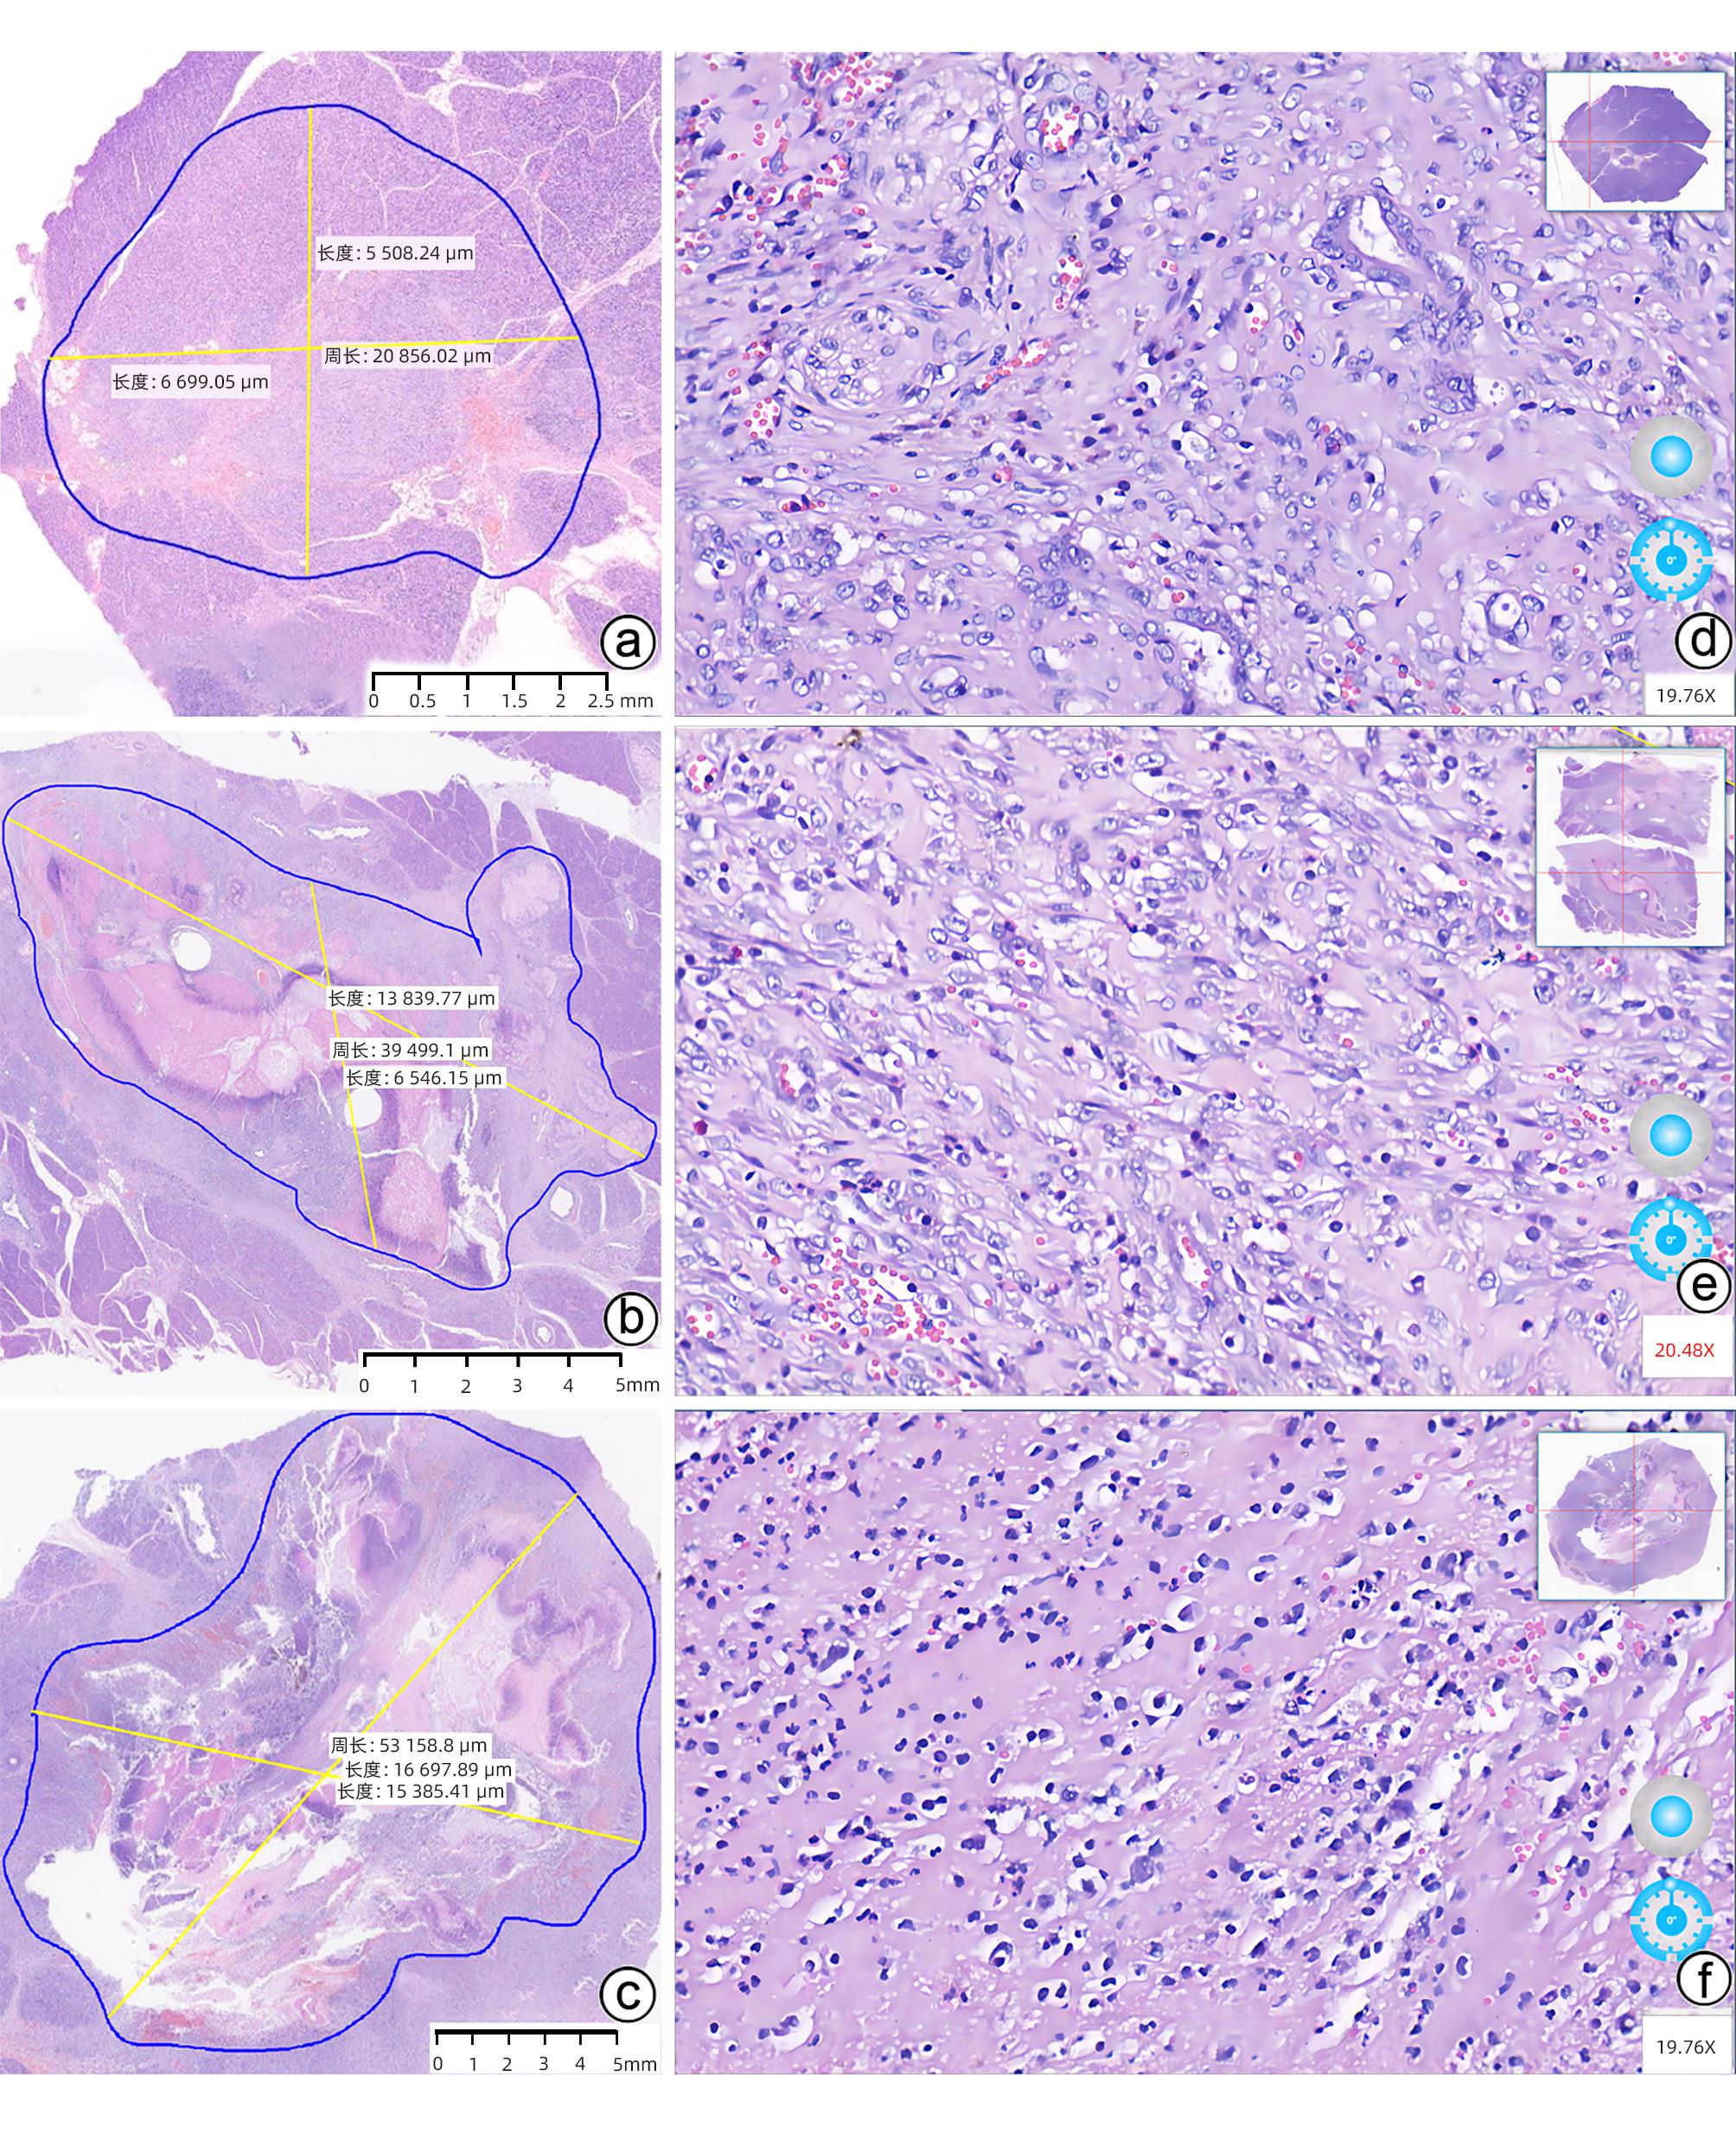

Standard for diagnosis and treatment of primary liver cancer (2024 edition)

2024, 40(5): 893-918. DOI: 10.12449/JCH240508